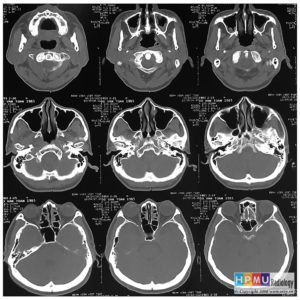

Chấn thương hàm mặt

Lượt xem: 275» 01-11-2018 -

Chấn thương hàm mặt

Lượt xem: 180» 01-11-2018 -